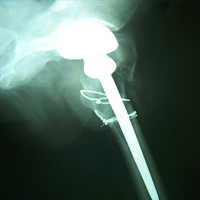

Case:7 Fracture Neck Femur with Implant failure and Re-Fixation with hemi-arthroplasty

Alcoholic Gardener by profession had slipped in bathroom & fell. He sustained fracture neck femur.He was operated with closed reduction & CC Screw fixation under IITV. Two weeks’ post fixation he again fell & sustained fracture in sub trochanteric region. He was treated with Hem-Arthroplasty with Tension band wiring.

Post-Op